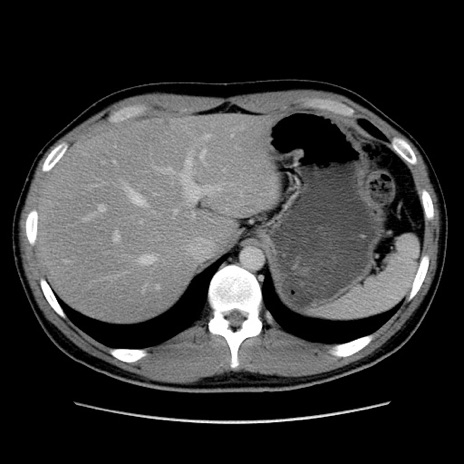

症例36(横断像)

冠状断像

【症例】20歳代 男性

【主訴】心窩部痛

【現病歴】今朝より上腹部痛あり。一旦軽快していたが再度出現したため救急要請。昨日夕に白身の魚を含む刺身を食べた。

【身体所見】BP 136/89mmHg、HR 74/min、BT 37.0℃、腹部:膨満、軟、心窩部に圧痛あり。反跳痛なし、筋性防御なし、腸雑音やや亢進あり。

【データ】WBC 17700、CRP 0.48